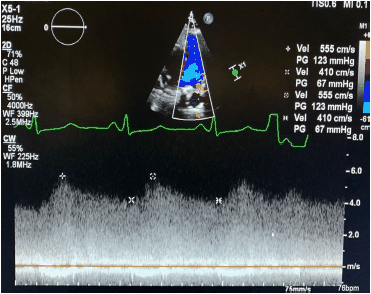

Uma gestante de 18 anos se apresenta para avaliação de sopro.

O sinal de fluxo registrado na imagem a seguir é compatível com

Enunciado 2141394-1